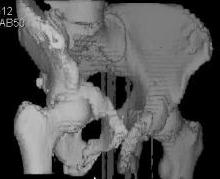

Уважаемые коллеги! Девушка 18л сросшиеся переломы лонных, седалищных костей с обеих сторон, перелом крестца справа,перелом костей голени справа (зио), 3 мес после травмы, АВФ снят с таза. Патологической подвижности нет. Стоит самостоятельно, ходит с костылями, поскольку 3 месяца практически не ходила. Беспокоит выступание лонной кости в области лобка, хотя объективно грубого косметического дефекта нет. На кт разворот лонной кости в сагиттальную плоскость. Вопрос: стоит ли добиватьсяполной репозиции или же достаточно произвести остеотомию верхушки выступающего отломка?

Предварительный диагноз- посттравматическая вертикальная нестабильная деформация таза II степени, неправильно срастающийся перелом боковой

массы крестца справа, правой лонной и седалищной костей, застарелый разрыв лонного сочленения.

Для уточнения диагноза ниеобходимы обзорные рентгенограммы таза (прямая и inlet), Кт срезы на уровне переломов для определения степени сращения и решения вопроса о методе оперативного восстановления анатомии (делать ли остеотомию, низводить ли задние отделы), ни о какой "остеотомии выступающих отломков" тем более у девочки 18 лет речи быть не может.